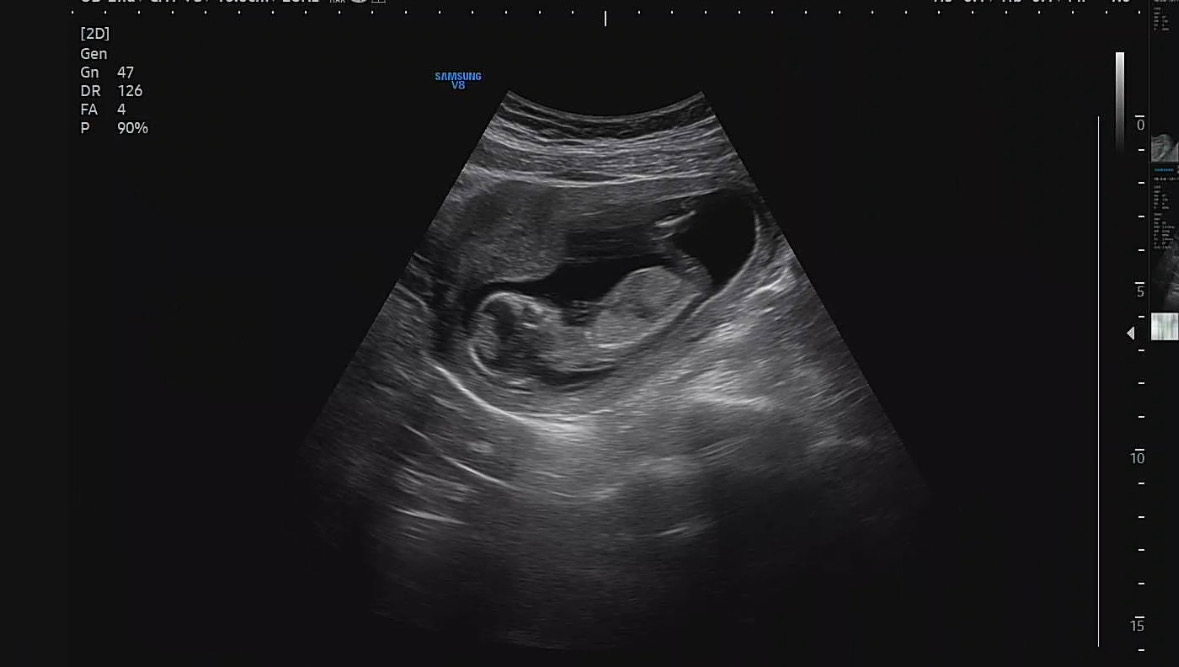

12주차 엽산 복용 ? 그리고 각도법 봐주세용 ~~

12주차 4일날 찍은 초음파 입니당 딸일까요 아들일 까용?? 그리고 의사선생님이 지금 부터 엽산 먹지 말라고 그러시던데 ᵕ̩̩ㅅᵕ̩̩ 다른 분들도 엽산 먹지 말란말 들으신분 있을까요?